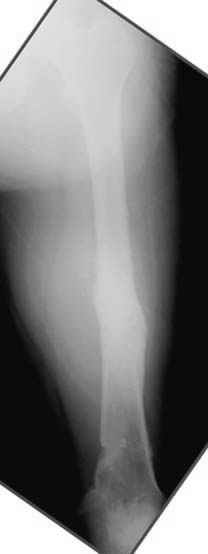

Отправитель: Djoldas Kuldjanov 23 Ноябрь 2004, 18:21

пластическая модель; и коррекция бедра аппаратом Илизарова.

Отправитель: Evgueny Tschekashkin 23 Ноябрь 2004, 21:28

Уважаемый Джолдас,

Почему не замена гвоздя с рассверливанием, а аппарат?

• Re: Hip joint

Отправитель: Alexander Chelnokov 23 Ноябрь 2004, 21:29

Попробую угадать - была инфекция?

Отправитель: Evgueny Tschekashkin 24 Ноябрь 2004, 21:09

хотя даже если бы и инфекция , то nail exchange с рассверливанием канала - вариант дебрайдмента) Я думаю, что последовательность развития событий:

Узкий к-м канал - тонкий гвоздь- усталостный перелом дистальных винтов - развитие нестабильности и как ее результат остеолиз вокруг гвоздя - деформация анатомической оси бедра. Похоже, что я понял почему аппарат, а не новый гвоздь:-)

[ Ответить ]

Отправитель: Alexander Chelnokov 24 Ноябрь 2004, 21:11

ET> Я думаю, что последовательность развития событий:

[...]

ET> деформация анатомической оси бедра.

Да, наверно. Но если ничего другого нету, ту небольшую деформацию можно было устранить дистрактором одномоментно ввести другой гвоздь.

Отправитель: Evgueny Tschekashkin 24 Ноябрь 2004, 21:13

> Да, но если, скажем, течет из инфицированных каналов запирающих винтов, да инфекция в дистальном метафизе бедра - устанешь сверлить.

ЕТ-Теоретически это возможно, а практически трудно представить - все-таки уровень медицинского сервиса высок, поэтому вряд ли инфекционное воспаление может зайти так далеко.....

ET> Похоже, что я понял почему аппарат, а не новый гвоздь:-)

> Тогда делись догадкой скорей!

ЕТ - Изначально костно-мозговой канал бедра был узкий, дальнейшее его рассверливание ещё больше скомпрометирует прочность бедра( латеральный кортекс дистального отломка уже истончен), приведет к дефекту наружной стенки - хотя это только мои догадки - хотелось бы знать мнение Джолдаса о выбранной тактике.